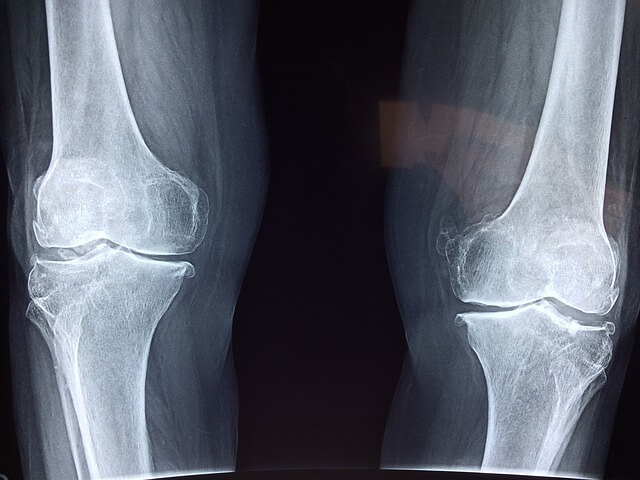

뼈를 연결하고 움직임을 가능하게 하는 관절은 문제가 발생할 때까지 그다지 눈에 띄지 않는 것이 특징입니다. 결국 불편함이나 통증을 느끼고 나서야 이상이 생겼음을 인지하게 됩니다.

관절 건강을 위한 방법을 이해하려면 관절의 복잡한 해부학적 구조를 먼저 알면 도움이 됩니다.

■ 관절은 두 개 이상의 뼈가 만나는 지점으로 무릎 및 팔꿈치와 같은 경첩 관절, 엉덩이와 어깨에 있는 볼-소켓 관절, 목에서 볼 수 있는 피벗 관절, 손목의 활주 관절 등이 있습니다.

■ 관절 건강의 핵심은 뼈 끝을 덮고 있는 연골에 영양을 공급하는 투명하고 점성 있는 액체인 윤활액이라고 할 수 있습니다. 이 윤활핵은 천연 충격 흡수 장치 역할을 하여 마찰을 줄이고 관절 표면의 마모를 방지하며 관절의 움직임을 보다 부드럽고 원활하게 하고 부상 위험도 최소화 해줍니다.

■ 연골은 관절 내에 있는 뼈의 끝부분을 덮는 완충재 역할로 뼈가 미끄러질 수 있는 매끄러운 표면을 제공하여 마찰을 줄이고 무게를 고르게 분산시킵니다. 나이가 들어도 통증이 없는 부드러운 관절 이동성을 위해서는 건강한 연골이 큰 역할을 합니다.

■ 인대는 뼈와 뼈를 연결하고 힘줄은 근육을 뼈에 연결합니다. 이러한 결합 조직은 움직임에 안정성을 제공하고 원하는 대로 움직임을 제어할 수 있게 합니다. 관절을 둘러싸고 있는 강하고 상태가 좋은 근육은 지지와 보호를 제공해 관절의 안정성을 유지하는 데 중요한 역할을 합니다.